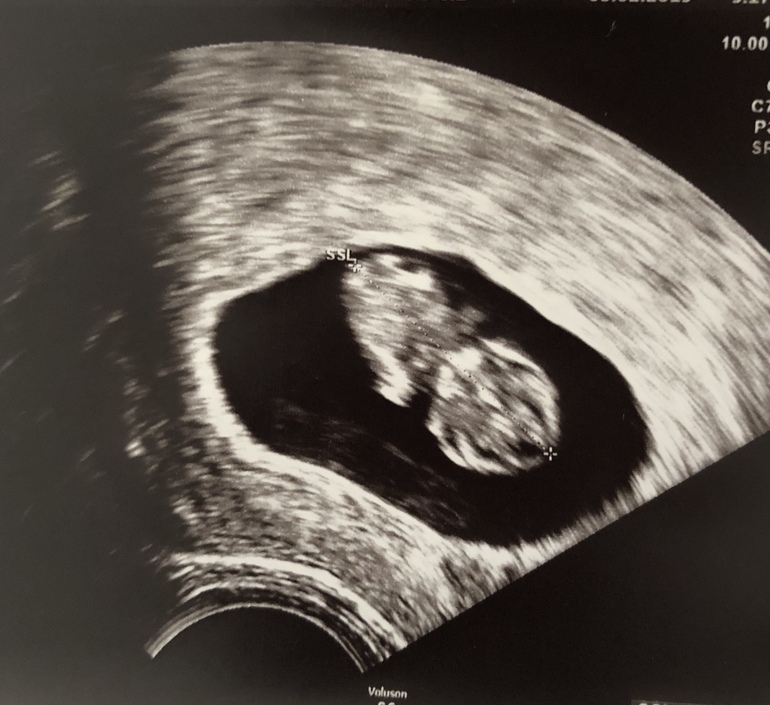

А в 8 с хвостиком работает еще?)

Это узи сына:

А вот первое узи с ним, на 5+5: